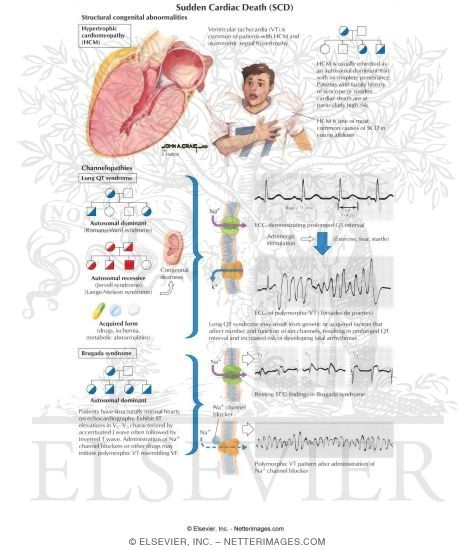

Sudden Cardiac Death

www.netterimages.comSudden Cardiac Death

www.netterimages.comSudden Cardiac Death